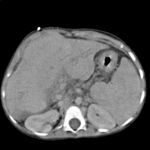

Bild 1. Computertomographie des Abdomens bei Leberzirrhose (Transversalschnitt).

Im Ultraschall stellt sich die Leber inhomogen dar. Der Leberrand ist wellig, die Binnengefässe sind rarefiziert. Der Lobus caudatus kann vergrössert sein. Sehr gut können mit dem Ultraschall ein Aszites und eine Milzvergrösserung (Splenomegalie) erkannt werden. Mit der Farbduplexsonographie lässt sich in den Lebervenen eine verminderte Elastizität der Leber, in der Pfortader ein verminderter Fluss sowie in der Leberarterie ein erhöhter peripherer Widerstand messen. Mit Sonar ist nicht immer eine definitive Diagnose möglich.